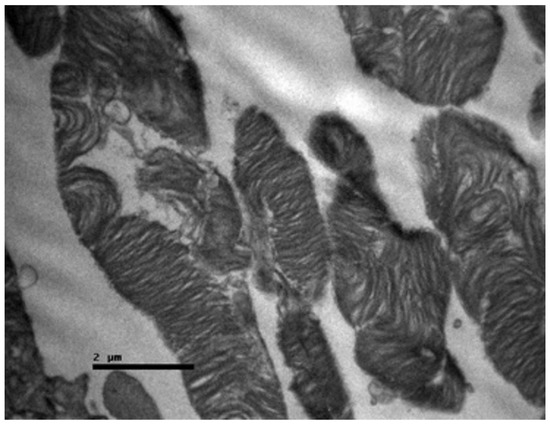

Background/Objectives: Cisplatin is a potent chemotherapeutic agent whose clinical utility is limited by severe side effects, including neurotoxicity affecting the ocular system. The pathophysiology involves oxidative stress and mitochondrial dysfunction, to which the retina is particularly vulnerable. Selenium (Se), an essential trace element and component of antioxidant enzymes, has shown potential in mitigating cisplatin toxicity, although its efficacy with respect to retinal structure and the influence of administration routes remain underexplored. This study aimed to evaluate the protective efficacy of selenium against cisplatin-induced retinal toxicity and compare the effects of intraperitoneal and oral selenium administration. Methods: Forty adult male Wistar rats were randomized into four groups (n = 10 each): Group A (Cisplatin Monotherapy, 3.5 mg/kg IP for 5 days; cumulative dose 17.5 mg/kg); Group B (Cisplatin + Intraperitoneal Selenium, 2.73 mg/kg; cumulative dose 60 mg/kg); Group C (Control); and Group D (Cisplatin + Oral Selenium). Selenium prophylaxis, administered as sodium selenite (Na2SeO3), began two days prior to cisplatin administration and continued for 15 days post-treatment. Retinal evaluation two weeks after cisplatin cessation included light microscopy, semi-quantitative immunohistochemical (IHC) analysis for inflammatory (IL-6) and fibrotic (TGF-β2) markers, and Transmission Electron Microscopy (TEM) for ultrastructural analysis, which were the primary endpoints. Statistical differences in the IHC scores were analyzed via the Kruskal‒Wallis H test with Dunn’s post hoc comparisons. Results: Cisplatin monotherapy (Group A) caused severe disruption of the retinal architecture, including edema, reactive gliosis, and significant upregulation of IL-6 and TGF-β2. Ultrastructural analysis revealed mitochondrial swelling (cristolysis) and photoreceptor disk fragmentation. Intraperitoneal selenium (Group B) was associated with significant structural preservation and intact mitochondria, with TGF-β2 levels comparable to those of the controls, although the IL-6 level remained moderately elevated. Conversely, oral selenium (Group D) suppressed both IL-6 and TGF-β2 expression to near-negative levels but provided less ultrastructural protection, resulting in persistent mitochondrial swelling and focal photoreceptor disruption. Conclusions: Systemic cisplatin induces severe subcellular retinal toxicity characterized by mitochondrial damage and photoreceptor degeneration. Selenium supplementation attenuates these effects; however, outcome patterns differ by administration route. Intraperitoneal selenium was associated with greater morphological and ultrastructural preservation despite persistent IL-6 elevation, whereas oral selenium normalized immunohistochemical marker expression to near-control levels but was associated with more pronounced residual subcellular damage on qualitative TEM assessment. These preliminary morphological and immunohistochemical findings suggest that the route of selenium delivery may influence its neuroprotective profile; however, pharmacokinetic measurements and functional retinal assessments, such as electroretinography, are warranted before its clinical translation. Full article